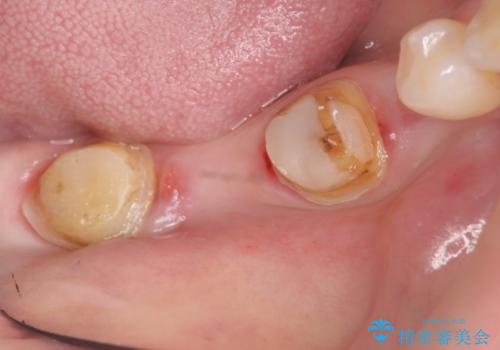

- 右下の奥歯の被せ物が外れてしまったので診て欲しいといらっしゃった方の症例です。

右下7は欠損しており、右下5は保存不可能だったため、インプラントによる欠損補綴を行いました。